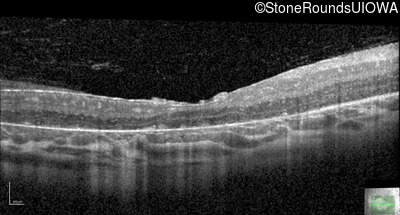

Optical Coherence Tomography - Right - 20/160

Exemplar / OCT Stack